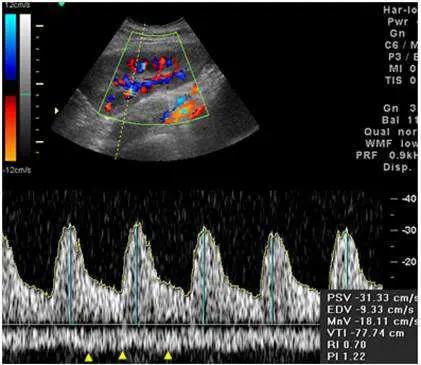

下圖為移植腎之彩色都卜勒超音波圖,下方黃色箭頭所指之頻譜為何?

本圖為移植腎彩色都卜勒超音波(color Doppler ultrasound of transplanted kidney):

彩色都卜勒影像(上半部):

- 移植腎呈扇形掃描區域,腎內可見紅色(朝向探頭)與藍色(遠離探頭)血流訊號分布

- 腎實質內血管分布正常,可見弓形及葉間血管樹

頻譜都卜勒(下半部):

- 頻譜主體呈基線以上的高起伏動脈型波形:有明顯收縮期峰值,舒張期維持正向血流

- 數據標示:PSV -31.33 cm/s、EDV -9.33 cm/s、RI 0.70、PI 1.22(速度值為負號,代表血流方向遠離探頭)

- 黃色箭頭(▲)指向基線以下的較平坦、低速、連續性波形

- 此基線下方波形:速度低(< 10 cm/s)、波形連續且平緩、無明顯搏動性起伏 → 典型靜脈頻譜特徵

比對動脈波形(基線以上)與靜脈波形(基線以下):兩者同時出現在同一取樣容積(sample volume)內,代表取樣閘門(gate)